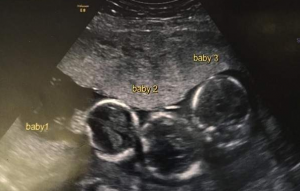

What initially began as a routine medical check soon became a moment she would never forget — she was carrying triplets.

Because of this, doctors scheduled an ultrasound earlier than normal. That decision led to a stunning discovery: three babies growing side by side.

The three boys — Rohan, Roman, and Rocco — were delivered by Cesarean section at 31 weeks and each weighed just over three pounds. Because they arrived early, they spent their first weeks in neonatal intensive care, where doctors monitored their progress closely.